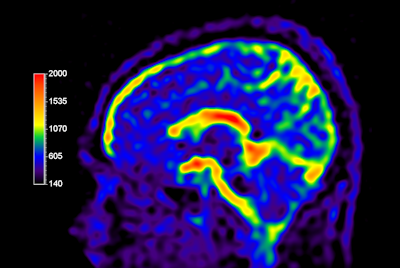

NeuroQuant